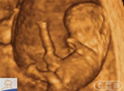

| Compre AgoraDe The Biology of Prenatal Development. |

Roteiro: Le mani ora possono unirsi così come i piedi. Sono presenti anche le rotule. |